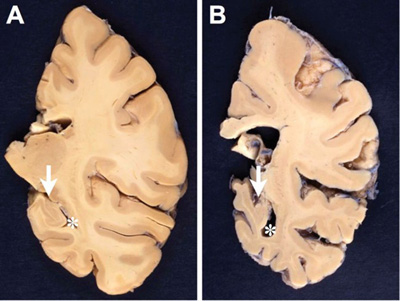

Figure 3. EM image of amyloid core of a neuritic plaque. Radiating bands of amyloid fibrils comprise the core (x). Note the adjacent abnormal fibrils filled with dense bodies (arrows) and surrounding damaged myelin sheaths (x 4000).